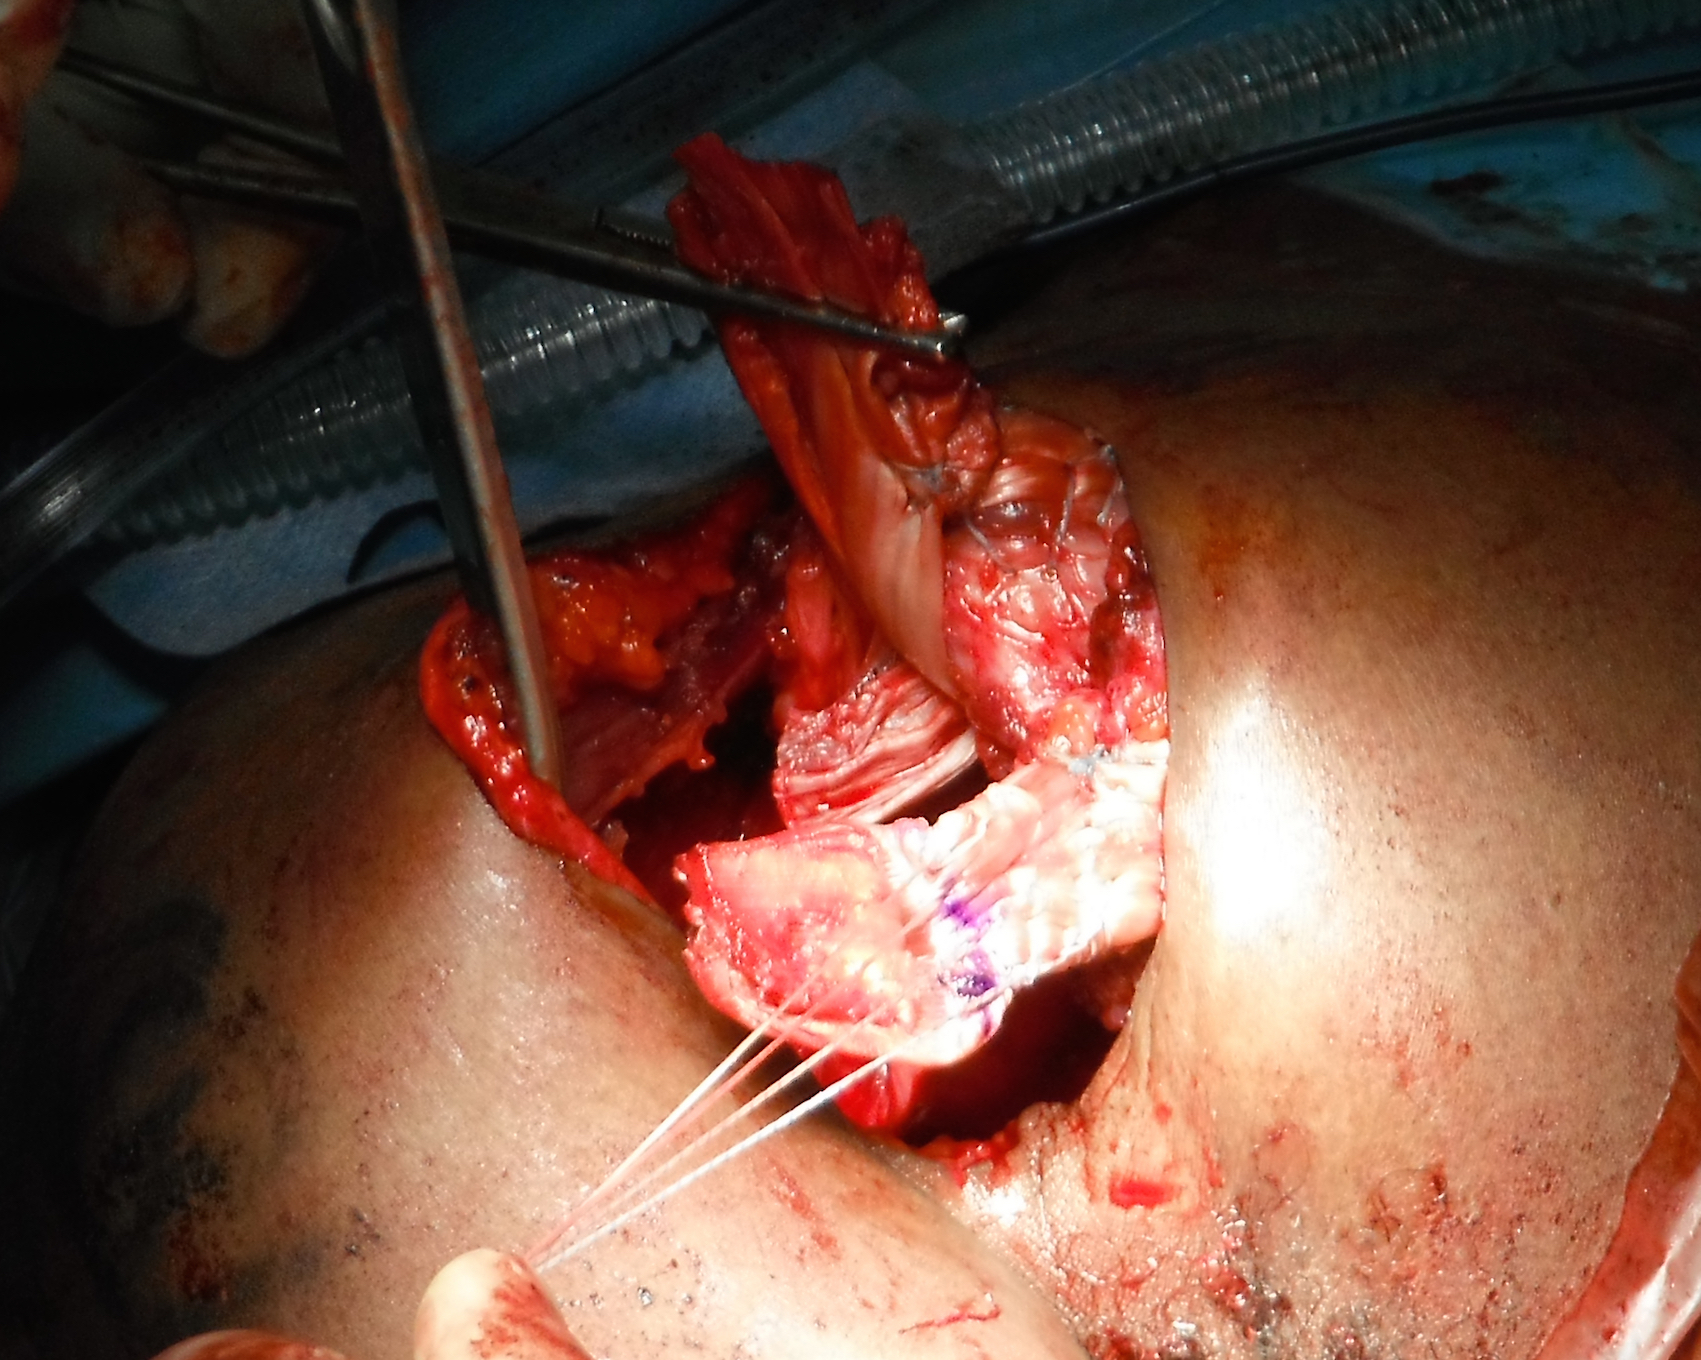

Pect Major Reconstruction 14 Suturing allograftPec Major Reconstruction 3

Right shoulder: allograft has been passed through sternal and clavicular muscle bellies and is being sutured back onto itself